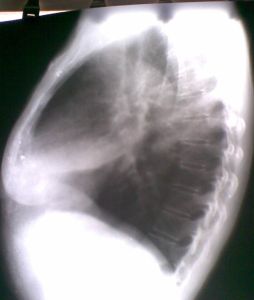

(1)胸部X線可見呈三角形的、均勻一致的陰影,尖端指向肺門,橫膈前方上抬,中葉容積縮小。